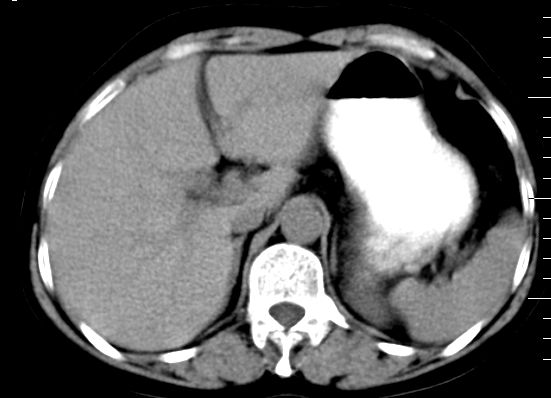

肝大小形态未见异常,肝内外胆管无扩张,肝s8段见一动脉期明显血管样强化结节,门脉期呈高密度,延迟期呈等密度,胆囊不大,增强扫描见胆囊及胆囊颈管壁增厚,有强化。

双肾灌注良好,代谢增快,动脉期肾盂见造影剂,左肾下极背侧见一略低密度病灶,延迟期见似不强化囊肿,双侧肾上腺未见异常。

2、肝s8段结节,考虑小血管瘤。

3、左肾下极低密度灶,考虑囊肿可能性大,建议随访,除外小肾癌(无强化可以基本除外)。

5.增强,脾特别明显是怎么回事?